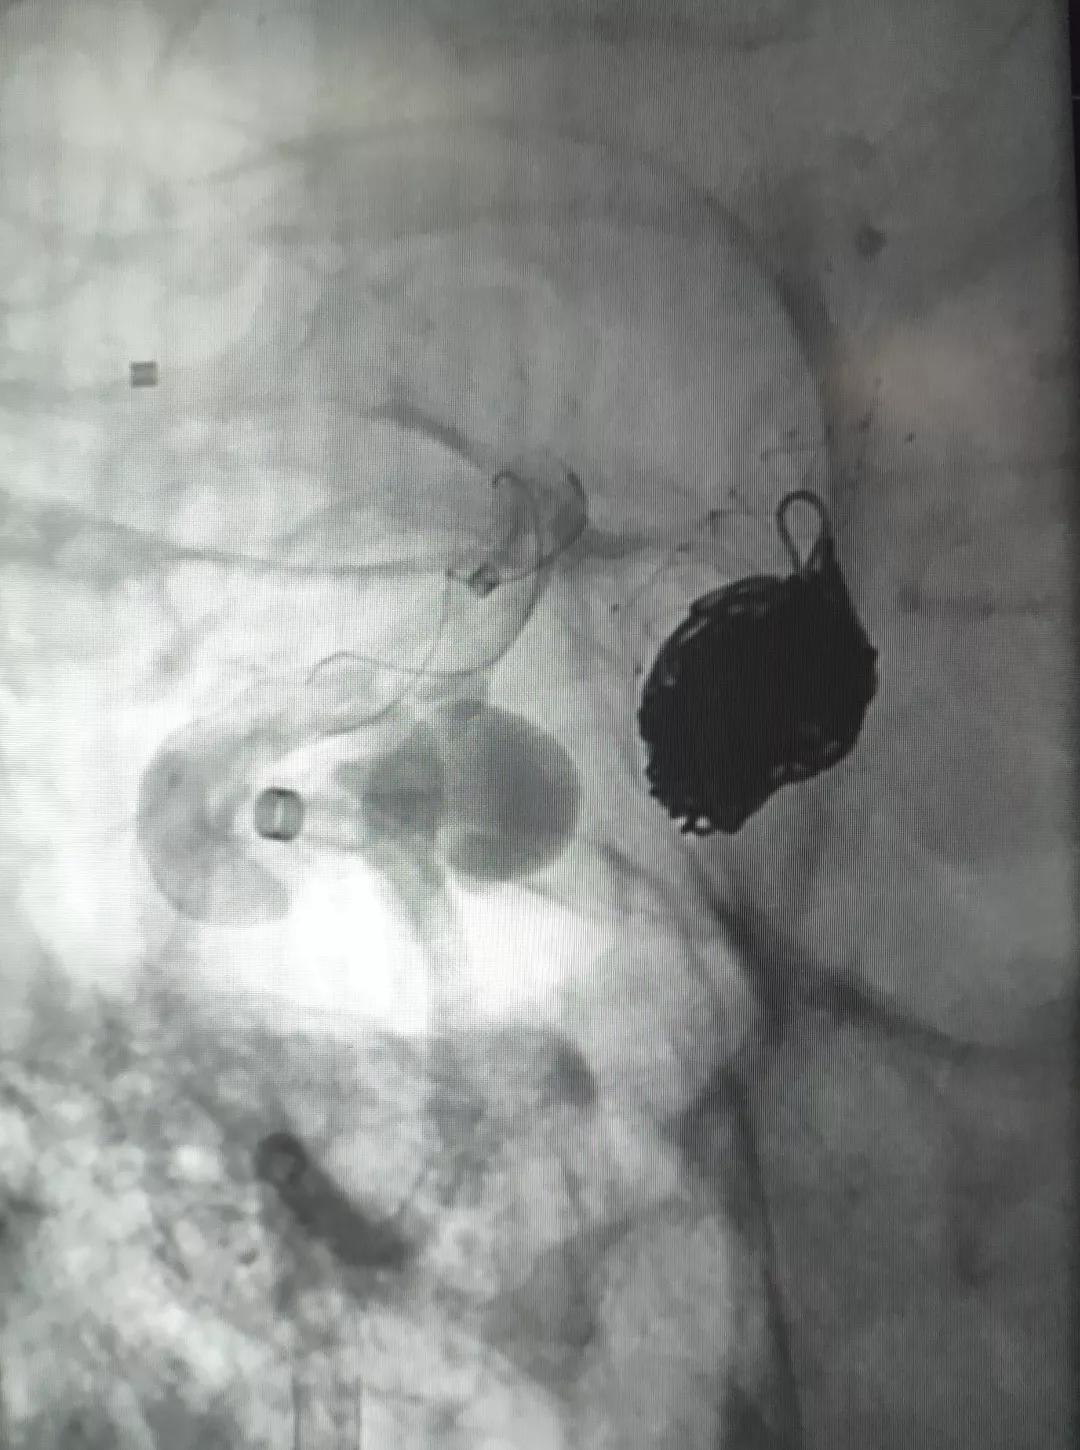

▲各角度观察显示Tubridge®贴壁良好

▲造影见造影剂滞留,载瘤动脉通畅。